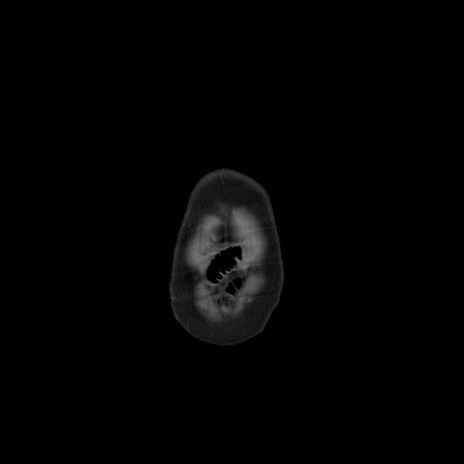

矢状断像